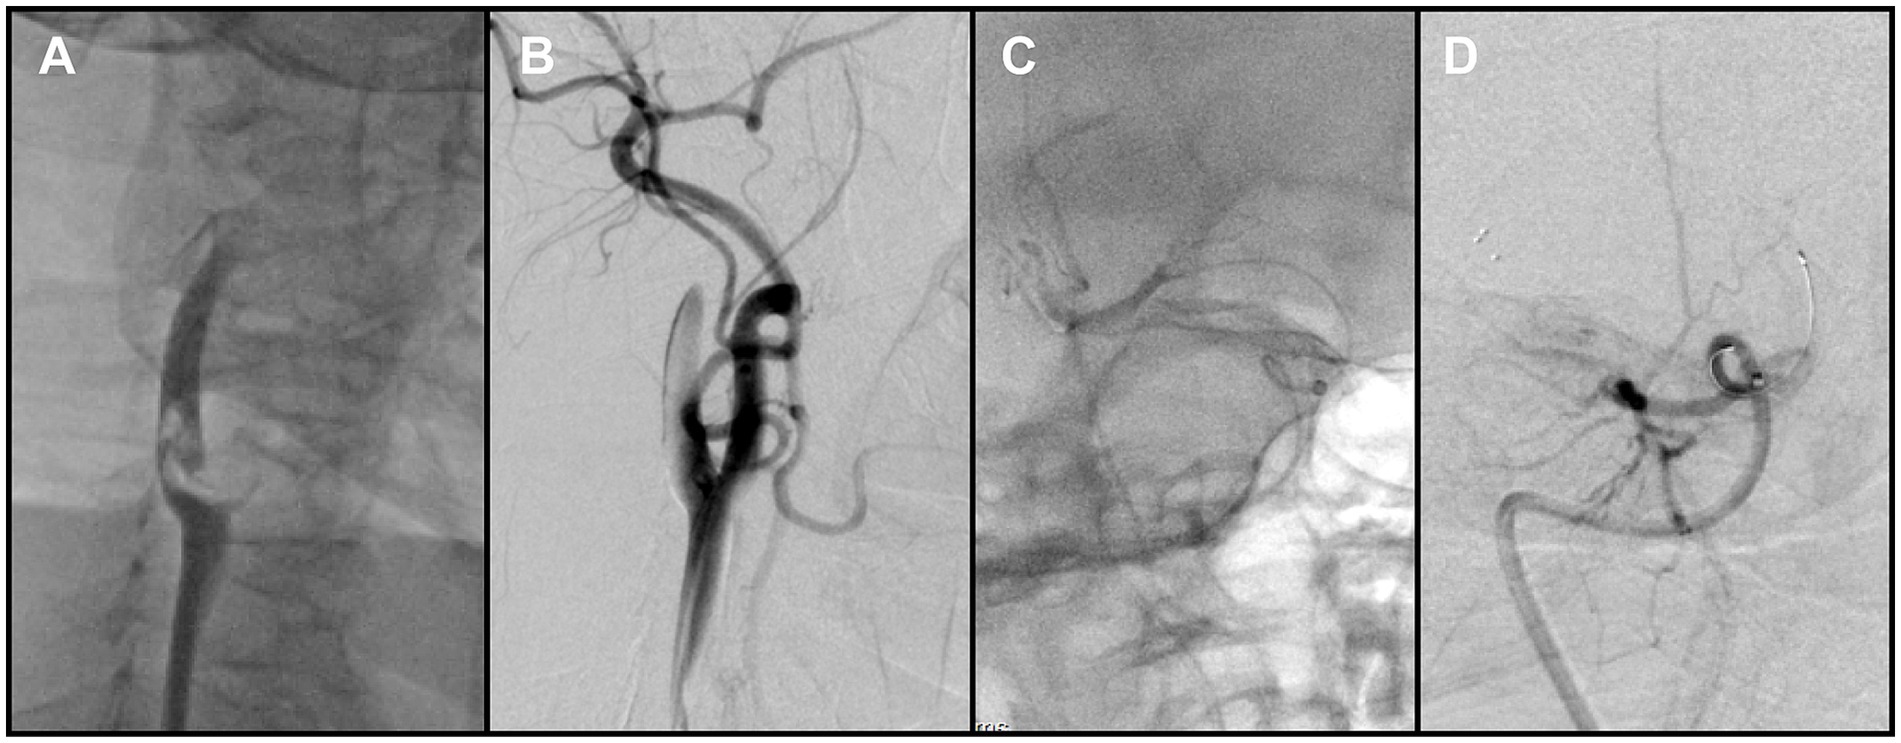

During this phase, impaired backflow in the Neuron MAX catheter was observed. After the catheter was withdrawn to the common carotid artery, adequate backflow through the guiding catheter was restored. Catheter angiography demonstrated severe vasospasm of the right ICA, explaining the earlier loss of backflow. In addition, a small residual thrombus was detected in the distal M1 segment (Figure 3A), and a previously unrecognized thrombus was identified in the right CCA (Figure 3B). After discussion, the team decided to prioritize treatment of the intracranial lesion. However, when the catheter was advanced into the ICA for follow-up angiography, the residual thrombus was found to have migrated spontaneously into an M4 cortical branch, and the ICA vasospasm had also resolved spontaneously. At that point, intracranial reperfusion was satisfactory, with an mTICI score of 2b, and no further treatment was required.

Figure 3. (A) Right common carotid angiography showed a small residual thrombus at the distal right middle cerebral artery (MCA) that did not significantly compromise hemodynamics. (B) A large thrombus was identified in the right common carotid artery, adjacent to the delivery catheter. (C) Brachiocephalic angiography with distal protection demonstrated a large free-floating thrombus (FFT) involving the brachiocephalic bifurcation, extending into the origins of the right common carotid and right subclavian arteries. (D) Post-stenting angiography demonstrated full expansion of the stent in the right common carotid artery (CCA), without residual stenosis at the treatment site.

2.4 Management of proximal FFT

To reduce the risk of embolization during assessment of the proximal vessels, a Solitaire stent retriever was temporarily deployed in the ICA to provide distal protection. As the Neuron MAX catheter was withdrawn to the brachiocephalic artery for angiography, a large FFT, corresponding to the lesion previously noted in the right CCA but only partially visualized, was clearly delineated at the brachiocephalic bifurcation, involving the origins of both the right subclavian artery and the right common carotid artery (Figure 3C). This thrombus at the brachiocephalic bifurcation was considered pre-existing, since no manipulation of the right subclavian artery had occurred before this angiogram.

Because en bloc retrieval across the bifurcation carried high risk of embolic escape and recurrent cerebral embolism, an in situ stabilization strategy was selected. Under distal protection with a SpiderFX device, a self-expanding PROTÉGÉ 9 × 40 mm stent (Medtronic, USA) was deployed in the CCA to pin and compress the thrombus against the vessel wall without predilation. Post-deployment angiography confirmed the ICA remained widely patent, with no residual stenosis (Figure 3D). The previously noted intracranial emboli had resolved spontaneously, and the final reperfusion grade improved to mTICI 2C (Figures 4A,B). Before completion of the procedure, angiography of the left vertebral artery demonstrated patent posterior circulation vessels with retrograde opacification of the right vertebral artery, indicating preserved collateral flow and minimal risk of thrombus migration from the right subclavian artery into the intracranial circulation (Figure 4C).

Figure 4. (A,B) Final angiography prior to procedural completion demonstrated reperfusion of the right carotid system (mTICI grade 2C). (C) Left vertebral angiography showed retrograde flow in the right vertebral artery. (D) Follow-up CTA at 1 month demonstrated persistent occlusion of the right subclavian artery.